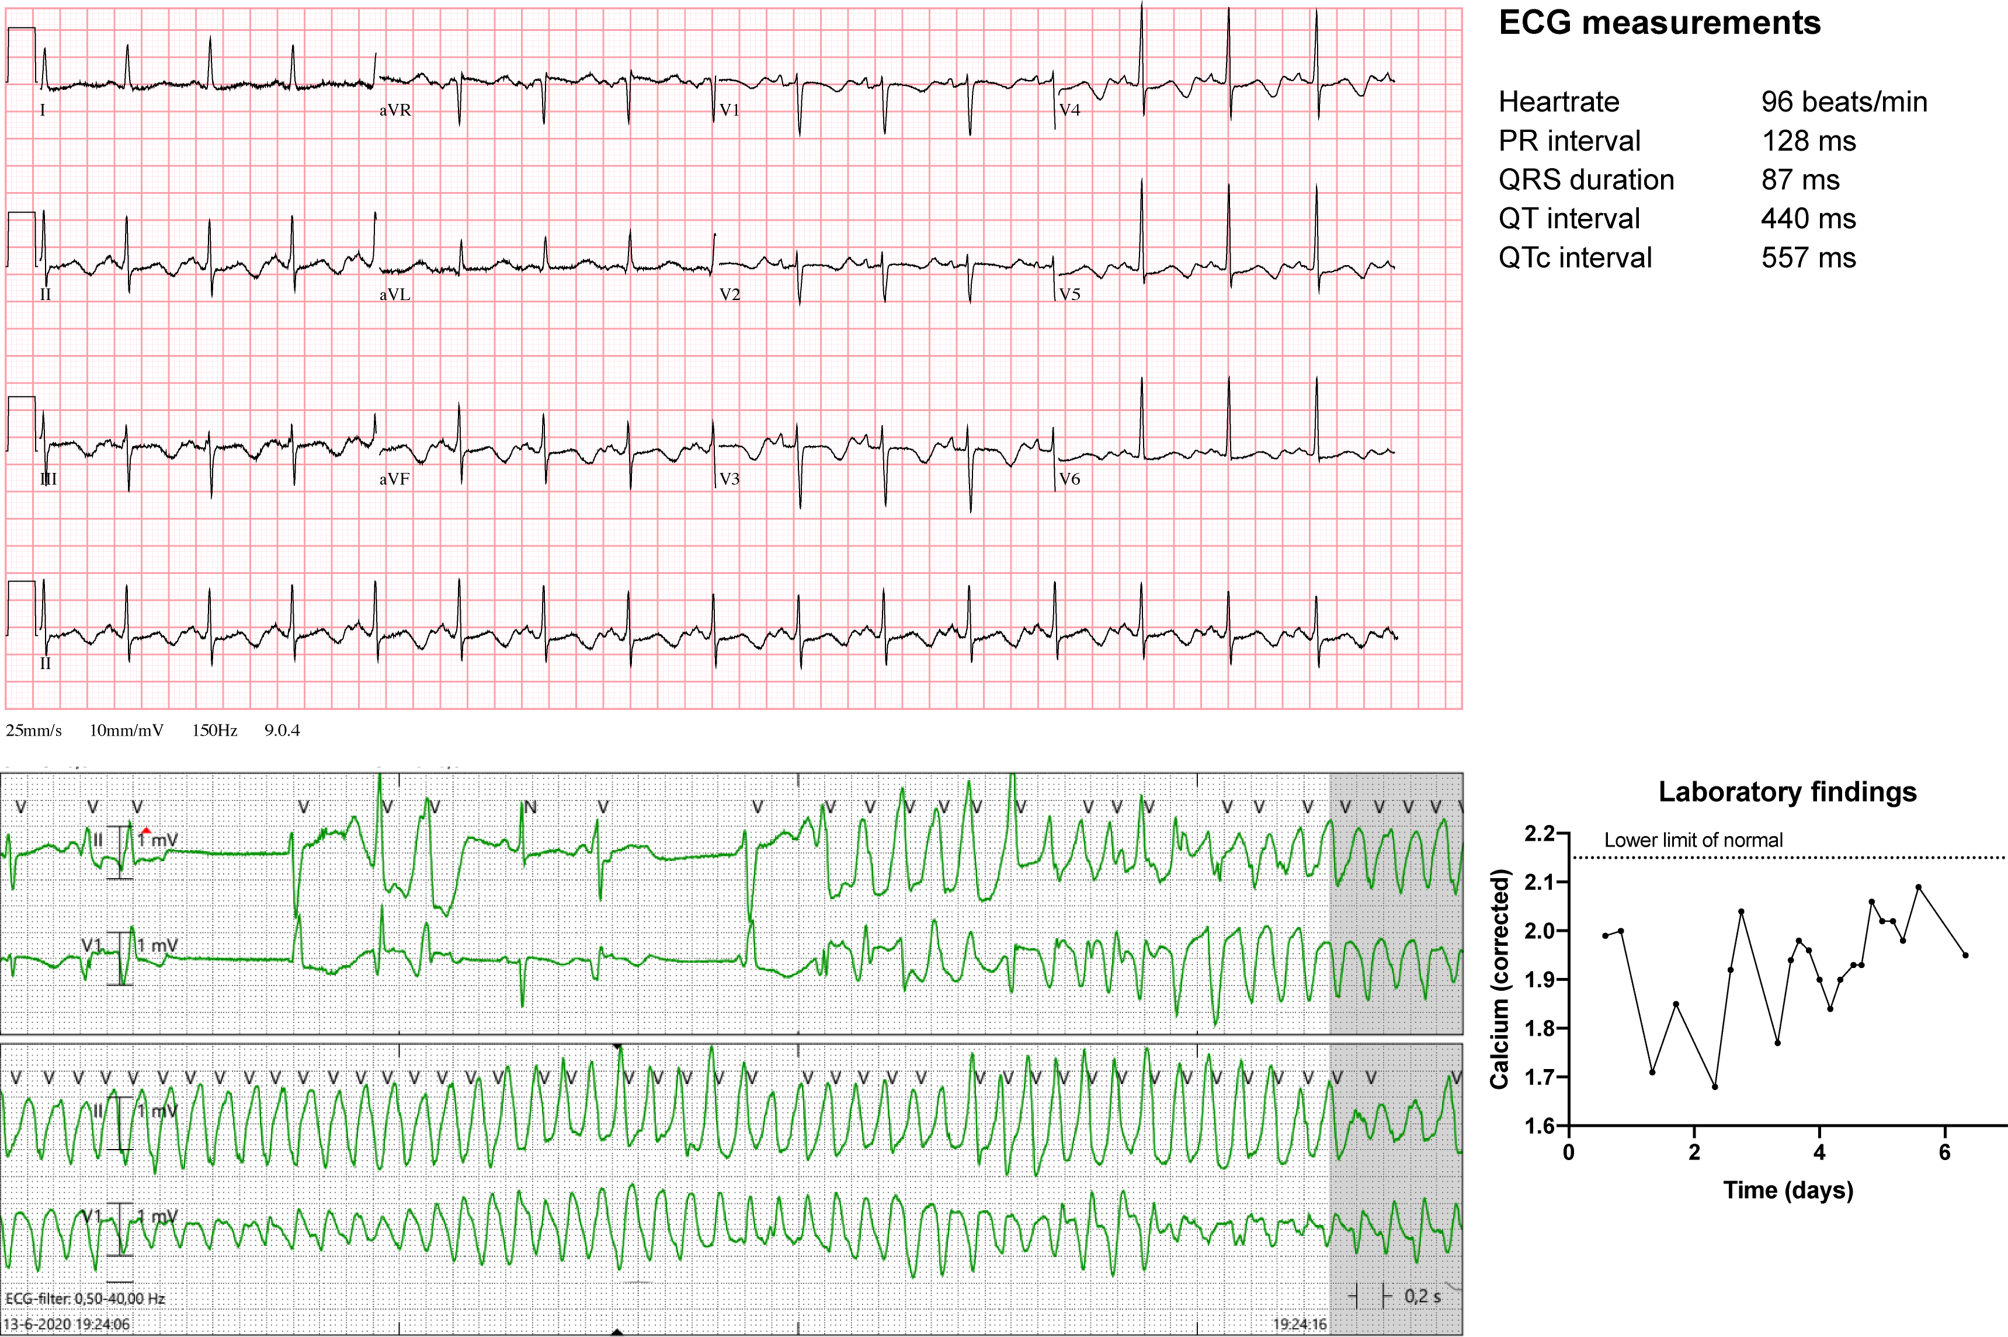

A 49-year-old, otherwise healthy female was admitted to our hospital for thyroidectomy. Postoperatively, presumably due to perioperative hypoperfusion of the parathyroid glands, she developed ‘hungry bone syndrome’, which is characterised by suppressed parathyroid hormone levels, resulting in an increased net bone uptake of calcium and subsequent severe hypocalcaemia [1]. Even with intravenous calcium supplementation, she developed QT prolongation and multiple episodes of torsades de pointes (TdP) ventricular tachycardia without cardiac output (Fig. 1). Isoprenaline was started to increase her heart rate to prevent further TdP. However, despite adequate heart rates (70–100 beats/min) and increasing, yet still subnormal, calcium levels, sustained TdP repeatedly developed, requiring electrocardioversion. She was transferred to a tertiary clinic, where her rhythm was successfully controlled by temporary tachypacing and high-dose beta-blockers. Chronic calcium supplementation eventually normalised her calcium levels and QT time.

Fig. 1

Upper Electrocardiogram demonstrating QT prolongation and ST‑T changes attributable to hypocalcaemia. Lower left Rhythm recording of the development of torsades de pointes ventricular tachycardia. Lower right Graph depicting the serum calcium levels over time